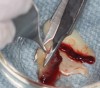

Fig 11. Schneiderian membrane perforation covered with a PRF membrane.

Figure 11